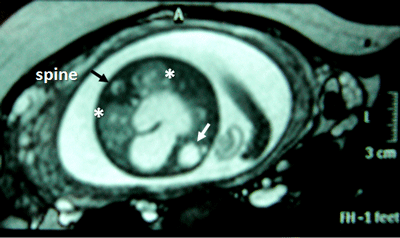

A 26-year-old pregnant women, gravida 1, para 0, was admitted to our prenatal diagnosis centre for detailed ultrasonography examination. Obstetric history was unremarkable. A single fetus was detected at 26 gestational weeks. A presacral located cystic mass measuring 45 × 55 × 40 mm was seen on ultrasound examination (Fig. 1). On doppler ultrasound, the cystic structure with both umbilical arteries around was considered an enlarged distally obstructed fetal bladder initially (Fig. 2). However, the bladder was later identified more superiorly. The amniotic fluid index was 129mm. Diagnosis of the cystic mass was unclear and a fetal MRI was performed, which delineated a large cystic mass with minimal internal echogenicity area, the type IV teratoma (big arrow head). The white arrow demonstrates a cystic mass considered as a hydrometrocolposis (Fig. 3).

Figure 1: The pelvic cystic structure (55 x 47 mm) with irregular borders. |